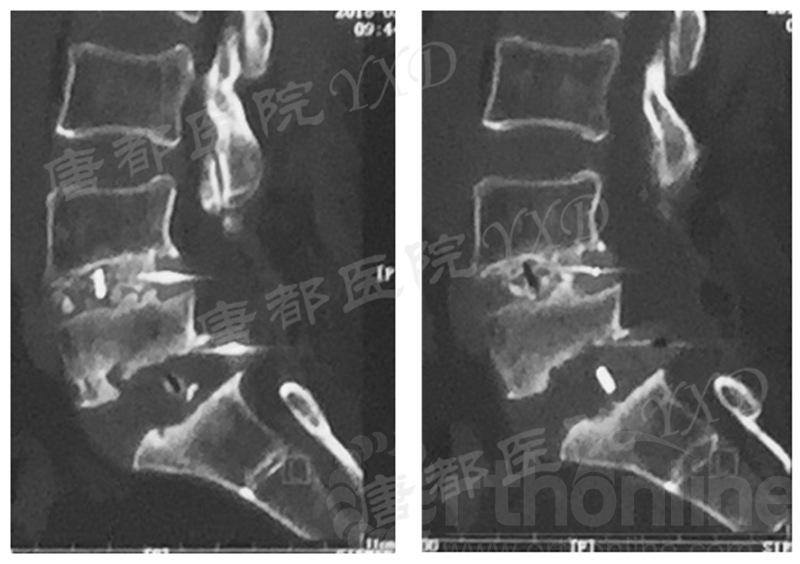

影像学检查:

诊断:腰椎椎间融合术后融合器后移

手术方案:显微镜辅助MI-TLIF腰椎翻修术

术中视频:http://api.orthonline.com.cn/attach/Case3.mp4(术中发现因前次手术全椎板及关节突切除,TLIF的第一步,即关节突关节的定位落脚点难以找到。显微镜下通过Kambin三角解剖位置,进行从外至内的解剖,寻找cage尾端;此外,因大量瘢痕渗血,难以进行充分止血;但在显微镜的照明和放大视野下,操作均可在不伤及神经的前提下进行。由于终板骨质吸收,椎间隙塌陷,导致术野内可同时看到出行根和走行根。而在显微镜下,能够通过调整景深和视线角度,精准充分处理椎间隙骨性终板。无手术并发症)